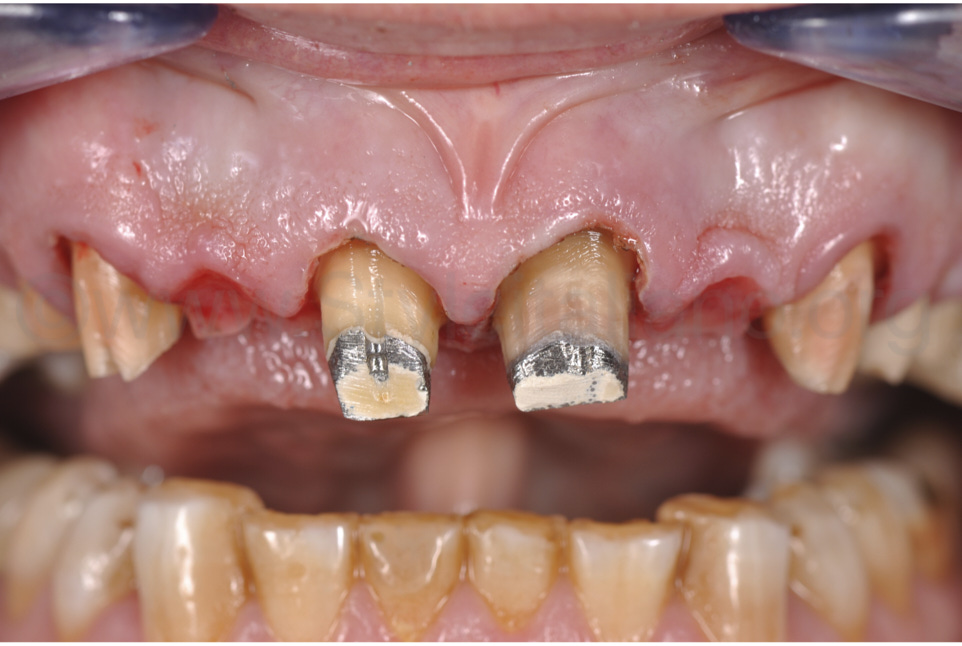

Фото 5.

Видалено старі реставрації, та виконано повторне препарування зубів і контурування ясен.